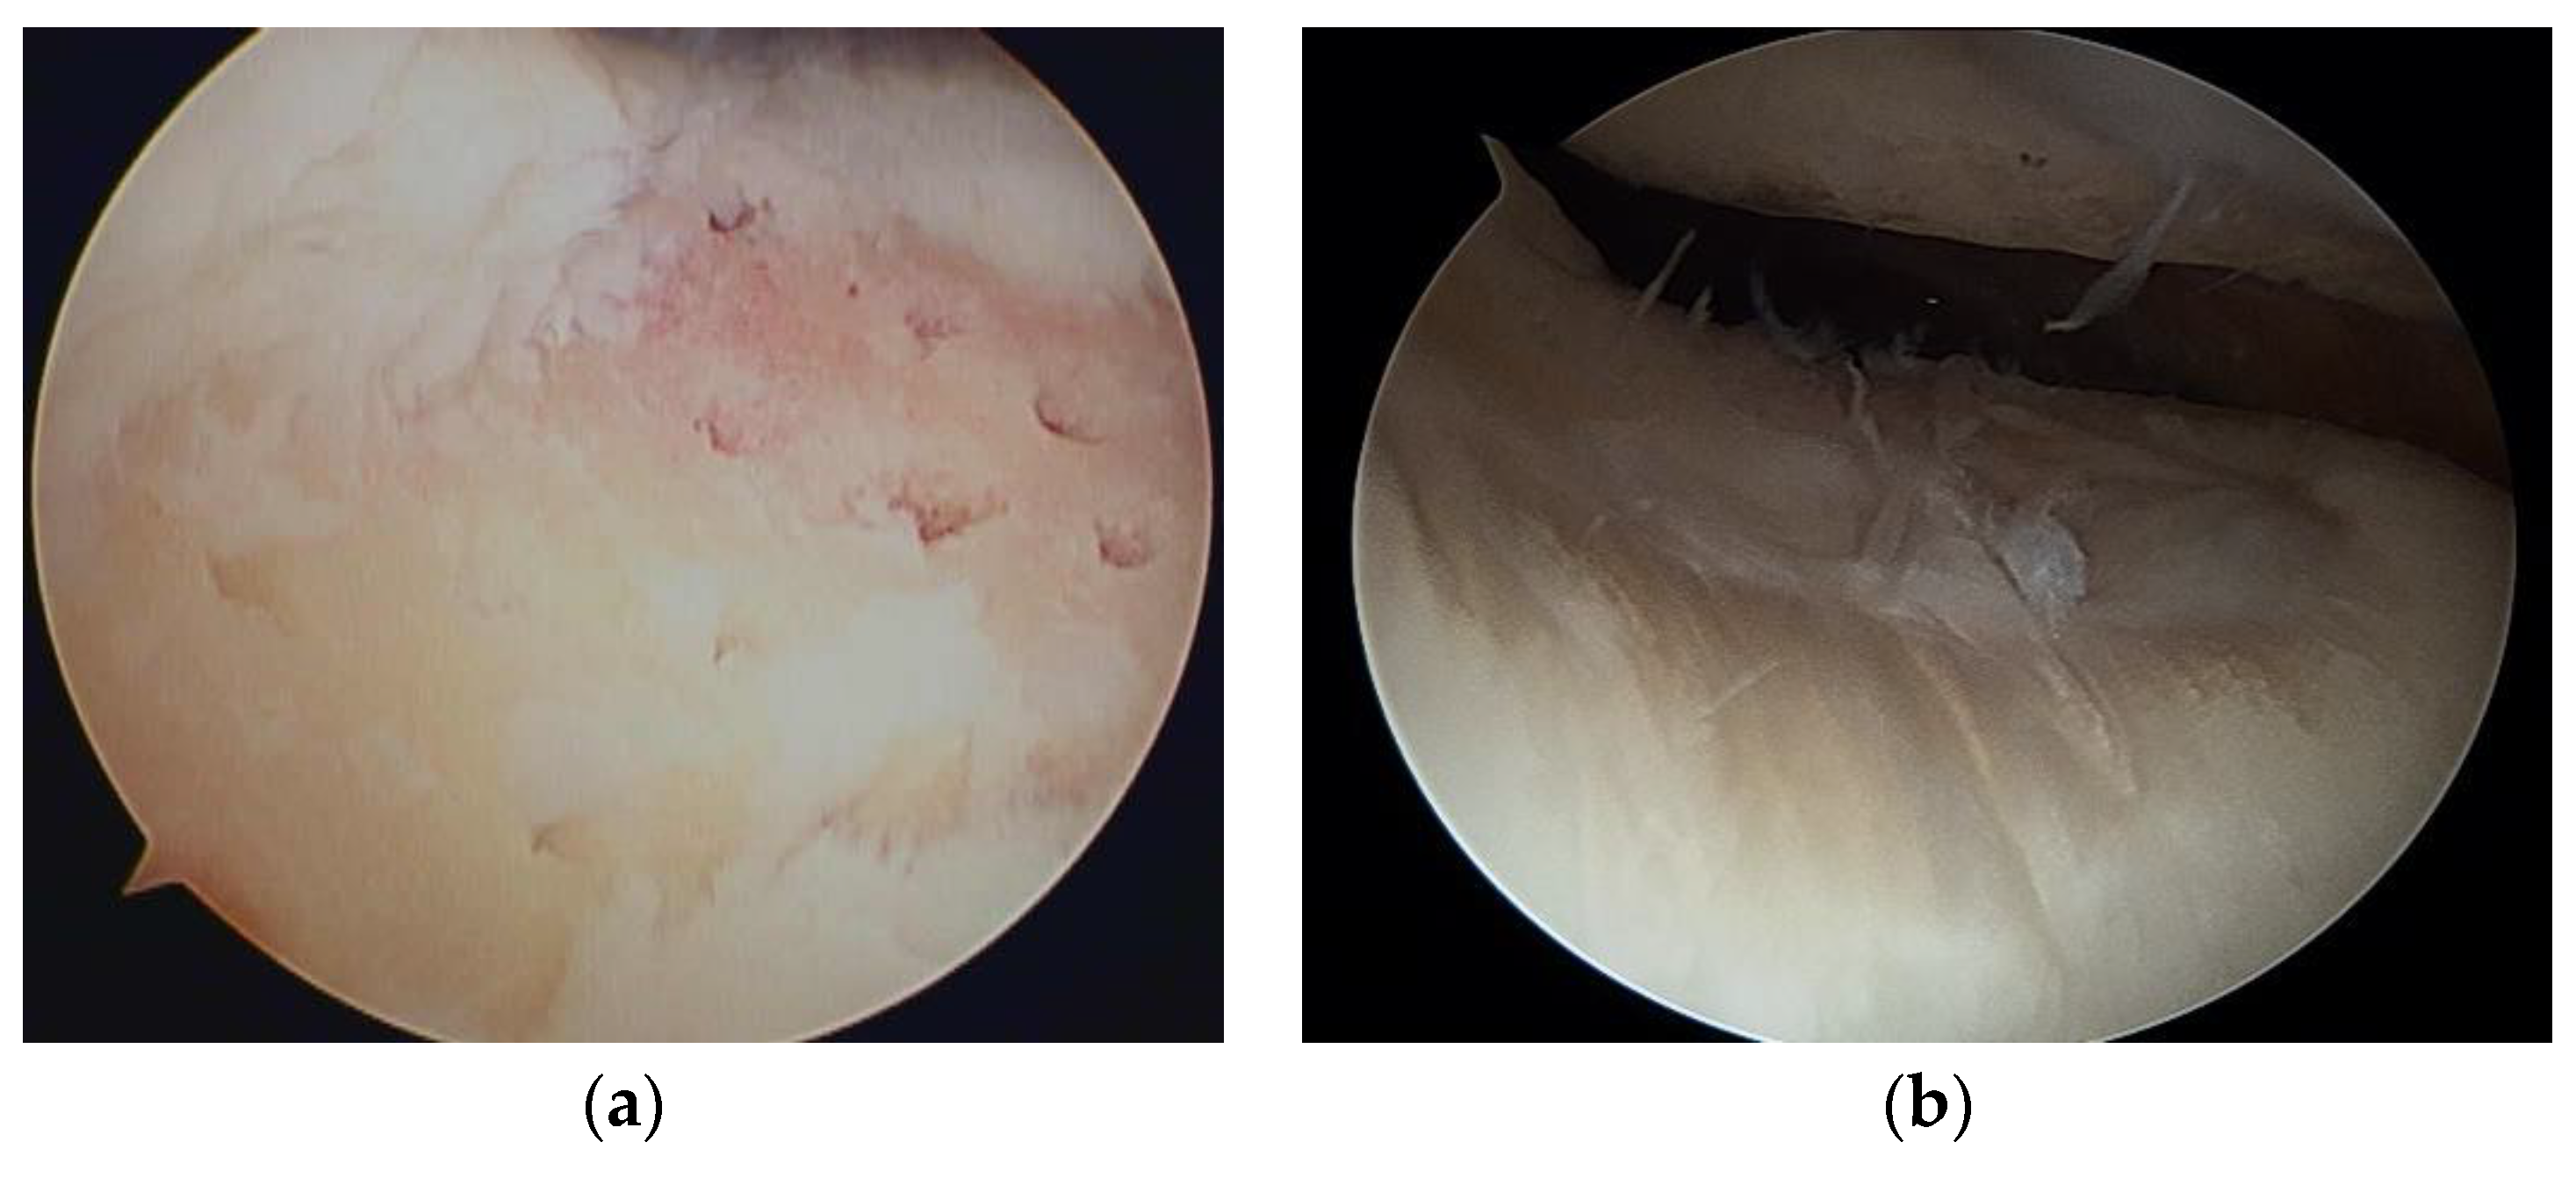

Steadman et al. [2] modified this method to avoid thermal necrosis from drilling, using bone marrow from the subchondral bone to form a clot on the defect holes (Figure 1). The clot contained mesenchymal stem cells (MSCs) and abundant growth factors, inducing repair by fibrous and hyaline-like cartilage [3] (Figure 2).

Figure 2. (a) Microfracture of a cartilage defect of the trochlea; (b) second-look arthroscopy 2 years later.